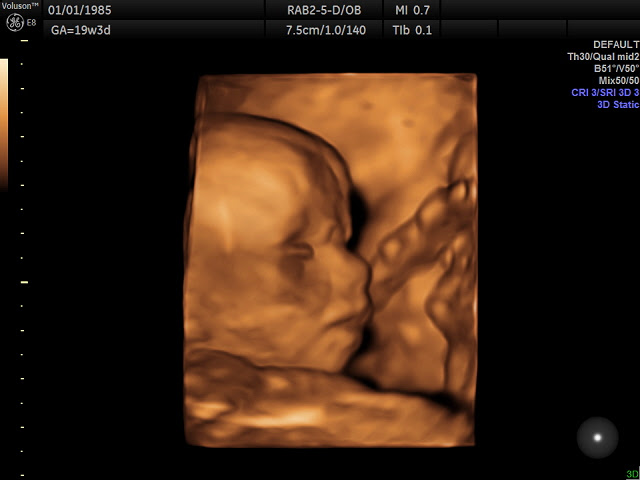

Well, as many of you know, we had our 20 week ultrasound of baby Frazier 2.0 on 28DEC15. What a special day that was! First and foremost, we found out that 2.0 will be another little girl! Boy did we surprise a lot of people! By the end of the tally we had 24 votes for a girl, and 35 votes for a boy!! The fun thing about doing the tallies is I have saved them for both this baby, and Novella, and they have been saved in their pregnancy journals along with ultrasound photos. When I was due with Novella, my mom passed down her pregnancy journal and my baby journal to me, I plan to do the same, as I try to document all that I can, so hopefully one day when they are bringing my grand babies (God willing) into this world that they can look back and see what it was like for their momma when carrying them! So it is a fun journey for me to document. So although I have not been actively blogging, I am still writing, so I cannot complain!

Onto the rest of our doctor appointment. Baby Girl 2.0 looks very healthy, and good. According to ultrasound photos she has a different forehead from Novella, but the same sweet mouth and lips. It is wild how much you can see and learn from ultrasounds these days! She however has a expected due date of 20MAY16, but is measuring to be due 21MAY16, which oddly enough is the day BEFORE Novellas second birthday! People joked and said maybe they would share birthdays, God only knows and it will be revealed to us in a few short months! The day of our ultrasound as we drove back from Green Bay, it began to snow, that night it snowed 13 inches in less than 12 hours with high winds that left snow drifts in our driveway up to four feet high! Talk about an extremely memorable day and night!